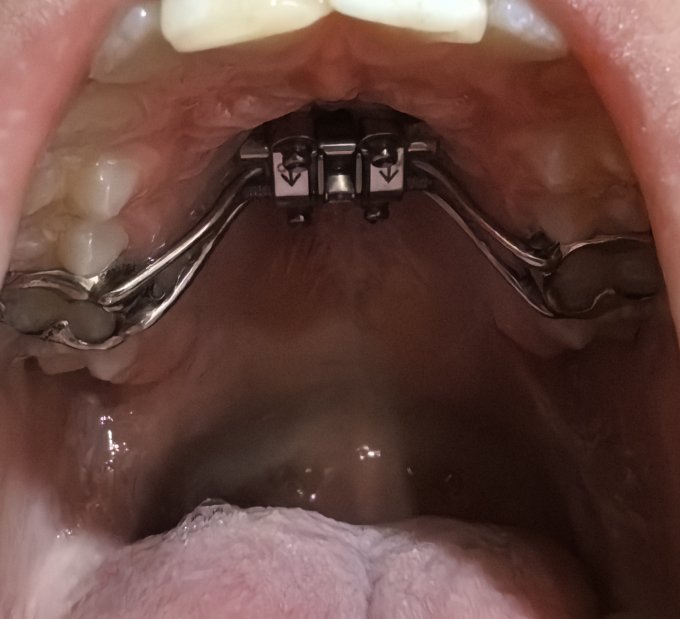

Моему старшему ребёнку поставили на верхнюю челюсть дистрактор, который расширяет верхнюю челюсть, разрыва её по небно-верхнечелюстному шву.

После консультации с врачами установлен дистрактор на верхнюю челюсть и теперь раскручиваем специальным ключом дважды в день, постепенно расширяя челюсть и добавляя место для зубов.

Анна, фиксируется на зубах и 4мя винтами в верхнее небо и посередине 6ти гранник его дважды в день крутим на 1 оборот